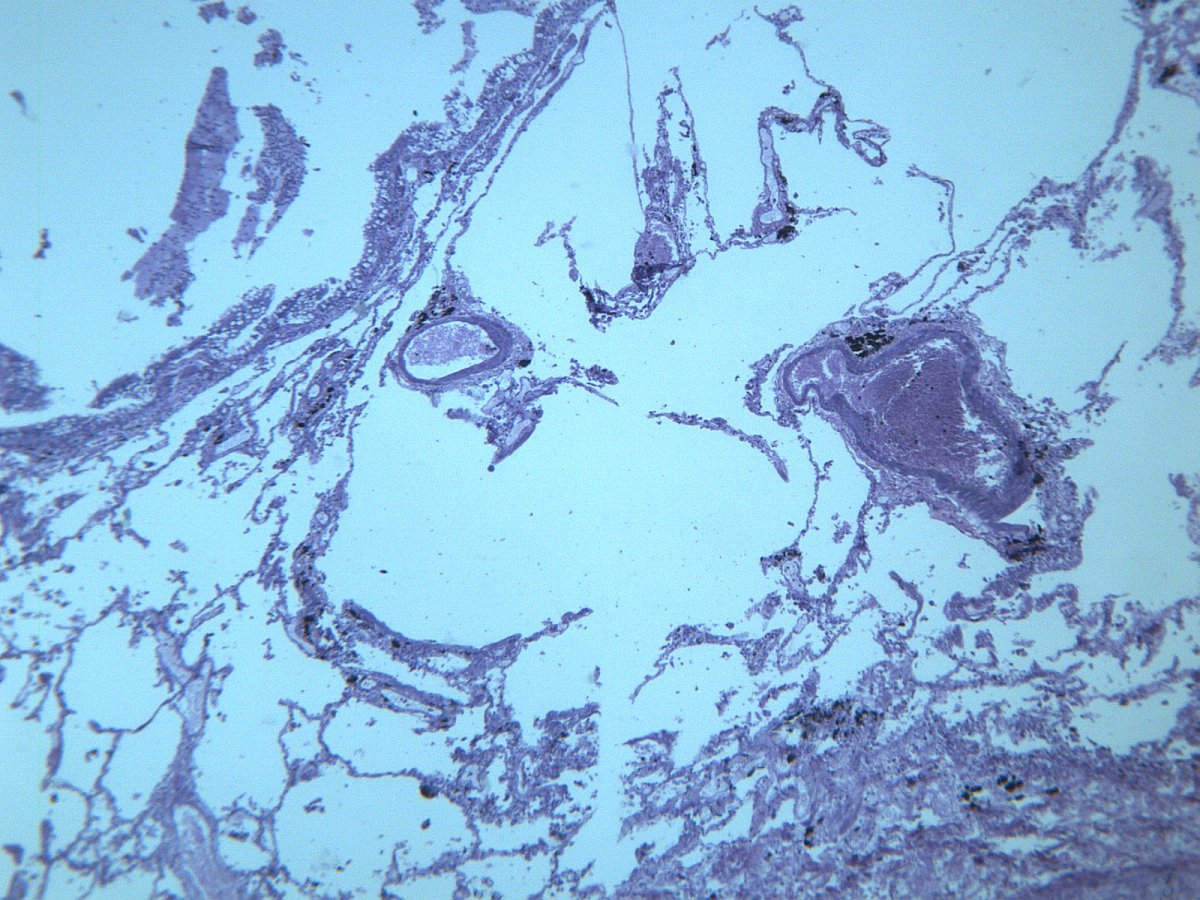

慢性支气管炎镜下图

慢性支气管炎不同部位显微镜放大

慢性支气管炎显微图片医学显微切片chronicbronchitis慢性支气管炎支